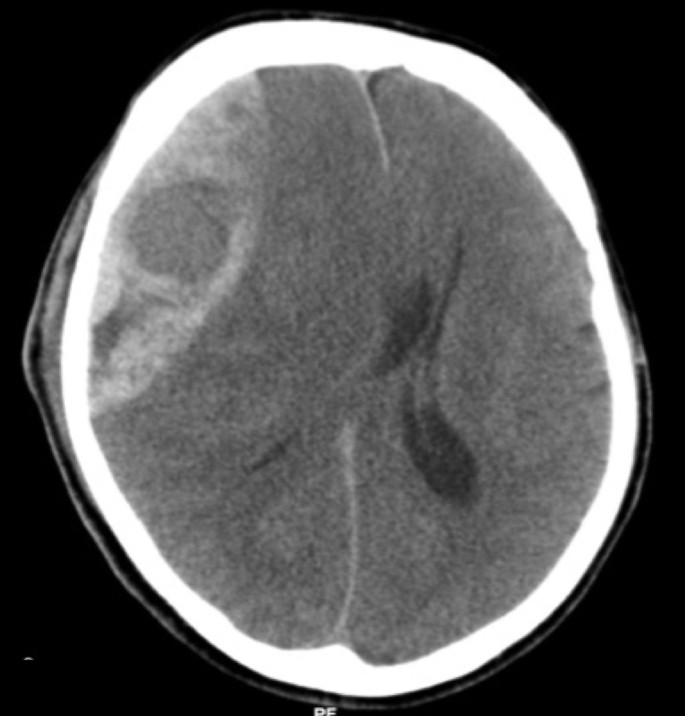

Внутричерепная гипотензия: КТ-исследования и их интерпретация

Раздел: Образы вокруг